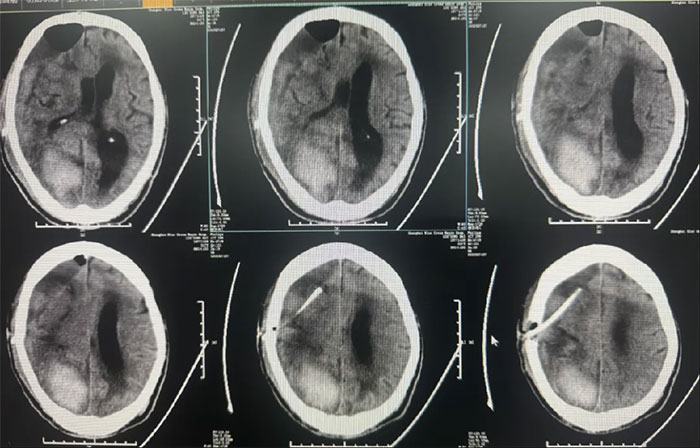

硬腦膜下鉆孔引流術(長程引流管),引流管自右側鎖骨下皮膚穿出引流;

2025-02-18(發(fā)病后17天);

手術情況:

患者病情復雜,選擇在局麻下進行,術程順利。

● 長程引流硬膜下血腫;

術后中線偏移明顯改善,顱內(nèi)壓降低,停用脫水藥物;